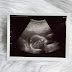

20 Weeks

Wednesday, April 26, 2017

I am no longer sick, but I was really expecting to get some energy back after we made it to the second trimester. I guess chasing a toddler around pretty much takes care of that. I am going to have my hands full once the baby arrives...he is already an active little thing. I have been feeling him move around for the last couple of weeks, and it is so much fun! And we got to see all of his squirming today, at our 20 week ultrasound.